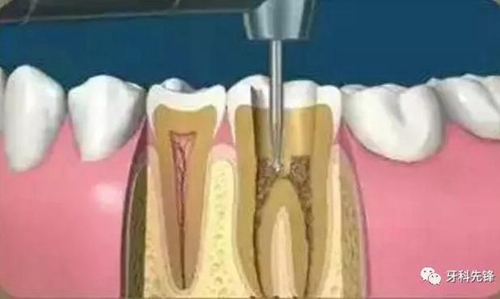

什么是根管治療

根管治療(root canal therapy)是牙髓病和根尖周病的國際上最常用的有效治療方法。根管治療術(shù)的原理是通過機(jī)械和化學(xué)方法去除根管內(nèi)的大部分感染物,并通過充填根管、封閉冠部,防止發(fā)生根尖周病變或促進(jìn)已經(jīng)發(fā)生的根尖周病變的愈合。

根管治療的步驟

4、根管預(yù)備

根管清理成形的目的是去凈根管壁上的感染物,通過根管器械的切削作用去除感染的牙本質(zhì)并清理根管壁細(xì)菌以利于根管充填。